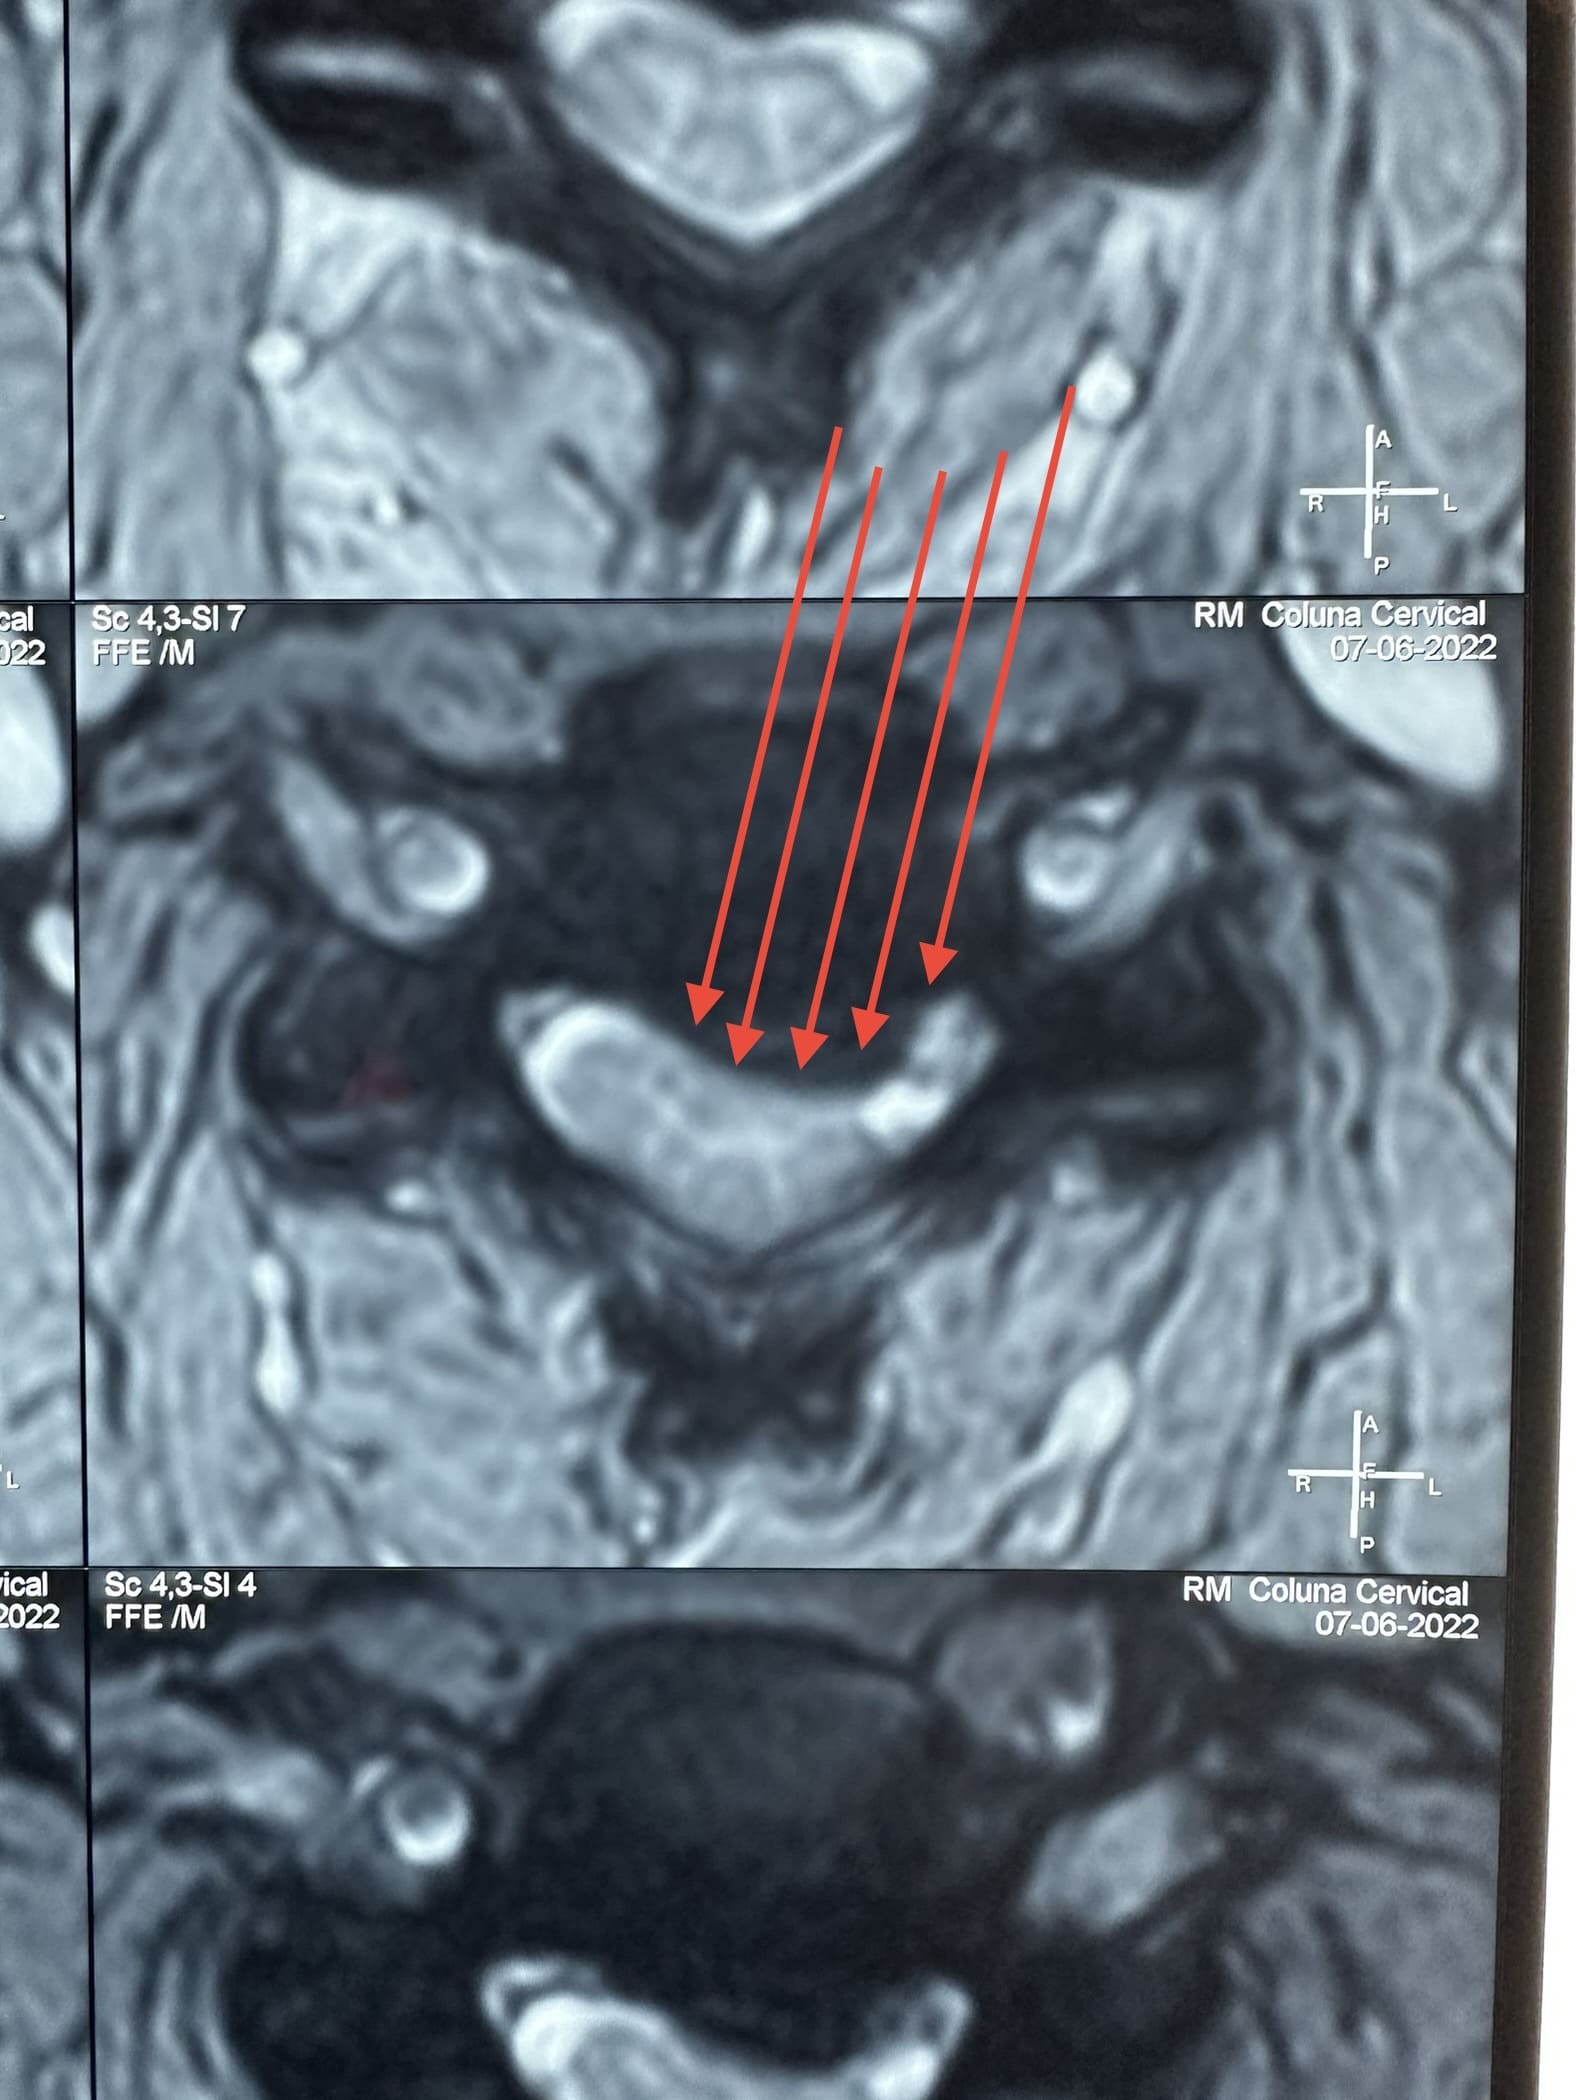

Uma hérnia de disco cervical ocorre quando o material do disco intervertebral se desloca ou se projeta para fora de sua posição normal e comprime as estruturas circundantes, como os nervos ou a medula espinhal.

Exames como ressonância magnética (RM), tomografia computadorizada (TC) e radiografias são frequentemente realizados para diagnosticar a condição da coluna cervical antes de decidir pela cirurgia.